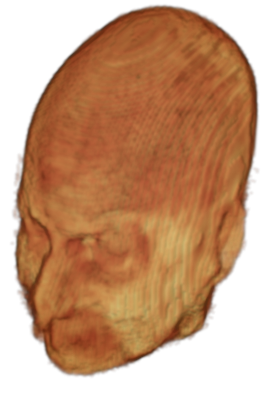

The digitalization of heath records has increased the risk of –and impact of– large scale data leaks. Although data compliance standards have been enacted to protect health records (HIPAA and GDPR), privacy of medical data is a growing concern. Three-dimensional scans such as magnetic resonance images (MRI) and computed tomography (CT), for example, contain an intrinsic privacy risk [Lotan et al.(2020)Lotan, Tschider, Sodickson, Caplan, Bruno, Zhang, and Lui]. Detailed renderings of the head can be crafted from 3D scans using techniques such as volumetric raycasting, as in Figure 1. This vulnerability can expose the patient’s identity if the renderings are matched to a face database [Mazura et al.(2012)Mazura, Juluru, Chen, Morgan, John, and Siegel, Lotan et al.(2020)Lotan, Tschider, Sodickson, Caplan, Bruno, Zhang, and Lui].

Therefore, in this work, we define a new class of de-identification techniques that remodels the privacy-sensitive regions without altering the content of medically relevant data (see Figure 1). Under such a remodeling approach, the face, eyes, oral and nasal cavities, etc. should exhibit realistic appearance and structure of appropriate size, but should otherwise be independent of the original data. To solve this task, we propose a novel model called Convex Privacy GAN, or CP-GAN, that conditions on a convex hull of the skull extracted from the scan to be de-identified. The generator learns to synthesize volumes that preserve medically-sensitive regions such as the brain, while non-invertibly remodeling privacy-sensitive characteristics from the original scan.